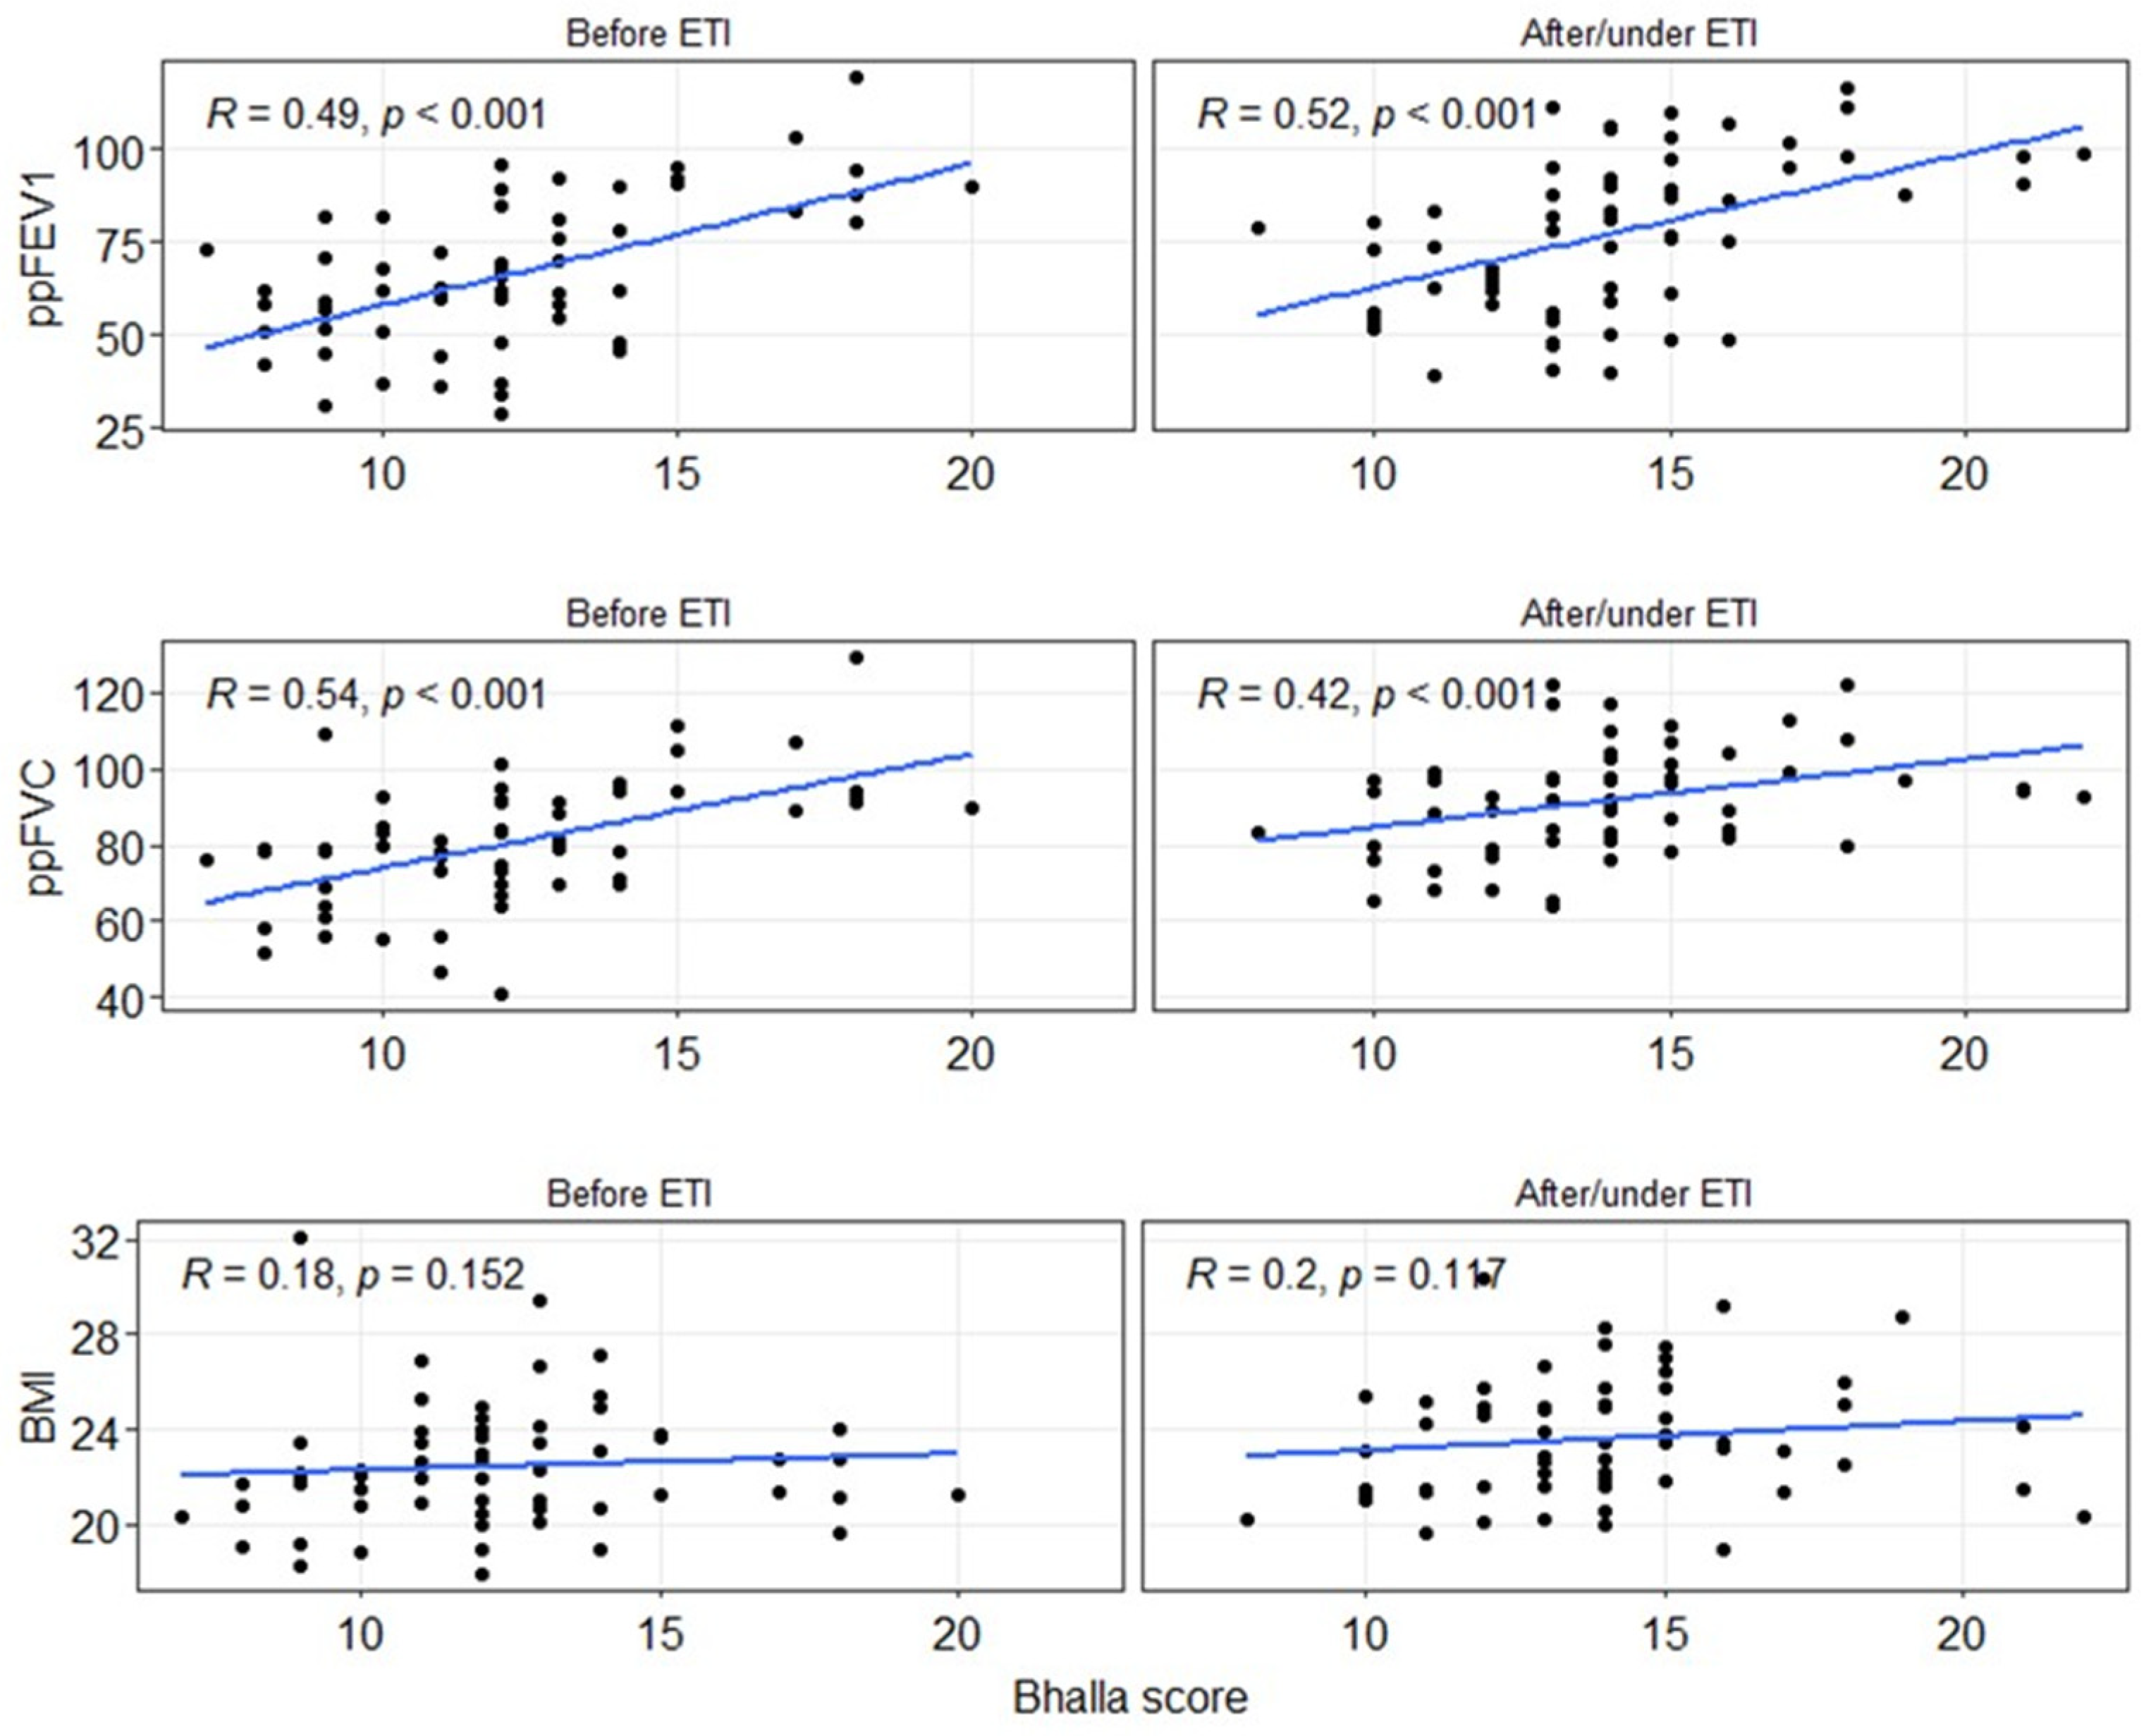

To assess the impact of ETI on lung function and BMI, correlation analyses were conducted between the Bhalla score, spirometry values, or BMI, both before and after ETI (Figure 3). A moderate and significant correlation (p < 0.001) was observed for the spirometry values, while no significant correlation (p > 0.05) was found for BMI. Regarding the ppFEV1 value, the correlation slightly increased after ETI (Rho = 0.49 to 0.52), although it remained within the moderate correlation range. In contrast, the correlation for ppFVC decreased (Rho = 0.54 to 0.42), but still remained within the moderate correlation range.

Figure 3.

Spearman correlation between the global Bhalla score, spirometry measurements (ppFEV1 and ppFVC), or BMI before and after/under ETI treatment. BMI: body mass index. ETI: elexacaftor–tezacaftor–ivacaftor. ppFEV1: percentage of predicted forced expiratory volume in the first second. ppFVC: percentage of predicted forced vital capacity.